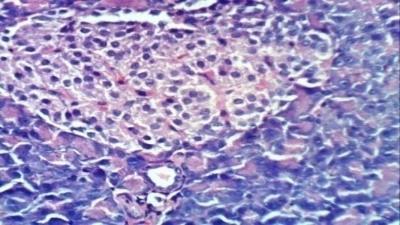

![]() |

Fig. 2 (c): Liver of diabetic rats treated with crude extract of F. japonica showed portal oedema (H & E X 400) | Fig. 3 (a): Kidney of normal control rats showed the normal histological structure of renal parenchyma (H & E X 400) |

Fig. 3 (b): Kidney of diabetic rat showed atrophy of glomerular tuft and thickening of the parietal layer of Bowman’s capsule (H & E X 400) |

Fig. 3 (c): Kidney of diabetic rats treated with crude extract of F. japonica showed congestion of renal blood vessels (H & E X 400) |

The biochemical parameters were documented with histopathological finding which reveal hydropic degeneration of hepatocytes, sinusoidal leukocytosis and congestion of hepatoportal blood vessel in diabetic rats (photo 2b). While the kidney of diabetic rat showed atrophy of glomerular tuft and thickening of the parietal layer of Bowman’s capsule (photos 3b and 3c). Also, Pancreas of diabetic rat exhibited vacuolation of epithelial lining pancreatic acini (photo 4d). Treatment of diabetic rats with ethanol extracts of F. japonica demonstrated normal histological structure in kidney and pancreas architectures (photo 3c, 4c and 4c), while portal oedema was reported in liver (photo 2 c).